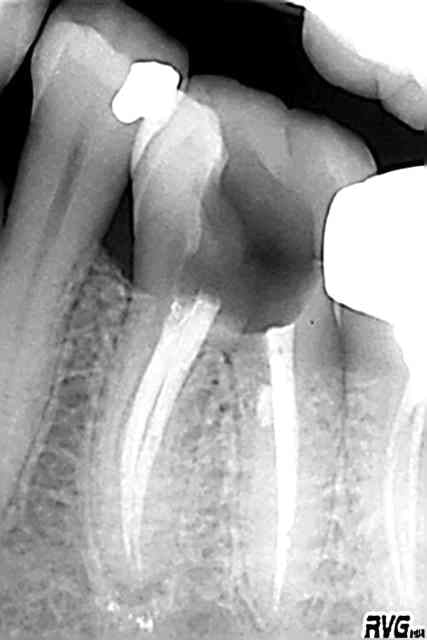

allez je vais te réconforter un peu : deux merdes en noir et blanc, prises à 2 ans d'intervalle, temps durant lequel ma patiente a oublié qu'elle avait un dentiste...

c'était bien la peine que je me défonce pour cette endo.

tu me diras, elle a accepté l'implant...